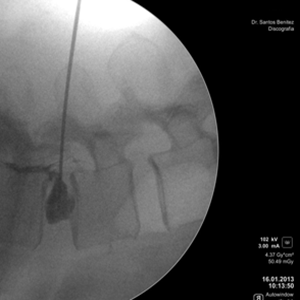

• Discografía percutánea